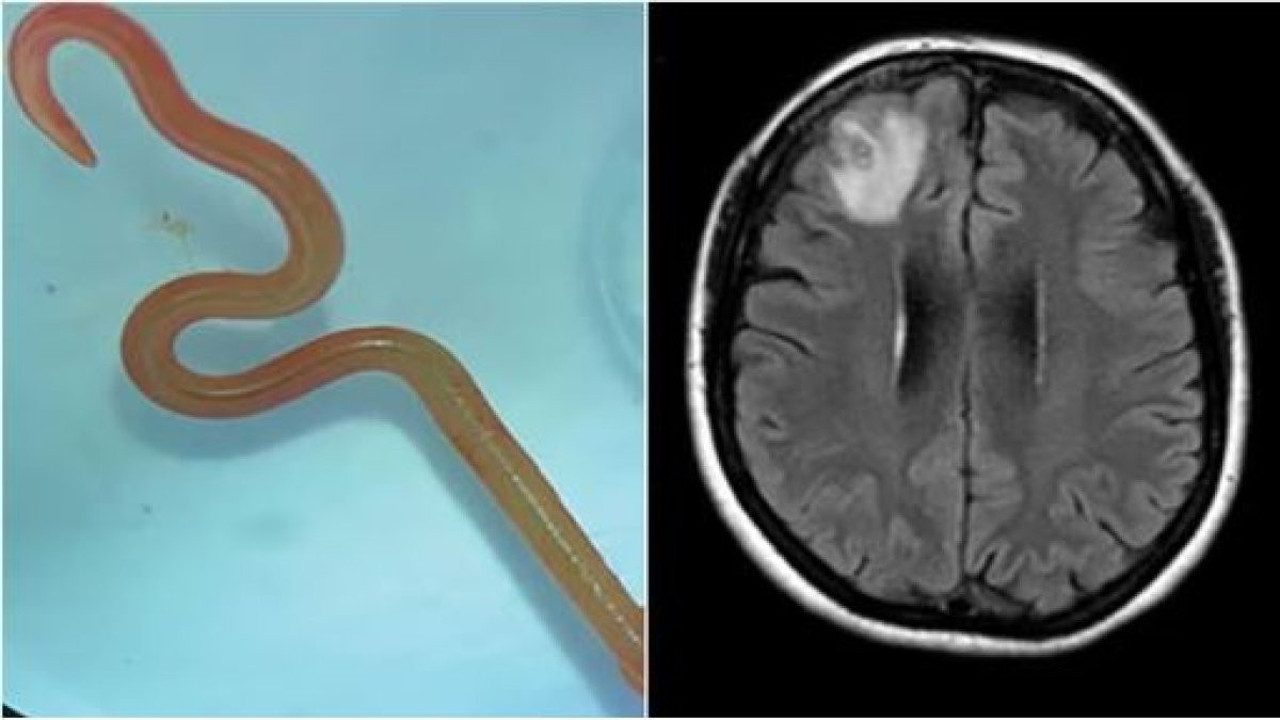

Avustralya’da 64 yaşındaki bir kadın, unutkanlık ve depresyon şikayeti ile hastaneye gitti. Yapılan incelemeler sonrası doktorlar kadının beyninde solucan olduğunu fark etti. Yapılan operasyon sonucu kadının beyninden sekiz santimlik canlı bir solucan çıkarıldı.

Kanberra Hastanesi'nde enfeksiyon hastalıkları uzmanı Dr. Sanjaya Senanayake, nörocerrah meslektaşı Dr. Hari Priya Bandi'yi telefonla arayıp hastasının beyninden 8 cm uzunluğunda canlı bir yuvarlak solucan çıkardığını söyledi ve daha fazla adım atmadan önce Senanayake ve diğer hastane çalışanlarından tavsiye istedi.

ÇIKARILAN SOLUCAN NORMALDE PİTON YILANLARINDA BULUNUYOR

Yapılan araştırma sonucu çıkan solucan türünün normal şartlarda piton yılanlarında bulunduğu tespit edildi.